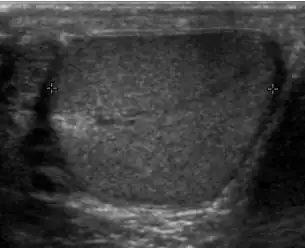

Sonography of a normal testis. The normal testis presents as a structure having homogeneous, medium level, granular echotexture. The mediastinum testis appears as the hyperechoic region located at the periphery of the testis as seen in this figure.

The normal adult testis is an ovoid structure measuring 3 cm in anterior-posterior dimension, 2–4 cm in width, and 3–5 cm in length. The weight of each testis normally ranges from 12.5 to 19 g. Both the sizes and weights of the testes normally decrease with age. At ultrasound, the normal testis has a homogeneous, medium-level, granular echotexture. The testicle is surrounded by a dense white fibrous capsule, the tunica albuginea, which is often not visualized in the absence of intrascrotal fluid. However, the tunica is often seen as an echogenic structure where it invaginates into the testis to form the mediastinum testis. In the testis, the seminiferous tubules converge to form the rete testes, which is located in the mediastinum testis. The rete testis connects to the epididymal head via the efferent ductules. The epididymis is located posterolateral to the testis and measures 6–7 cm in length. At sonography, the epididymis is normally iso- or slightly hyperechoic to the normal testis and its echo texture may be coarser. The head is the largest and most easily identified portion of the epididymis. It is located superolateral to the upper pole of the testicle and is often seen on paramedian views of the testis. The normal epididymal body and tail are smaller and more variable in position.